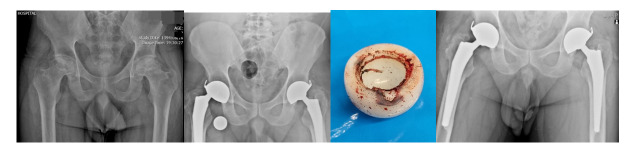

Results: A total of 163 patients (168 hips) underwent THA with DMC, with a mean age of 58 ± 5.3 years. Five patients had bilateral total hip surgery. The average follow-up time was 48 ± 5.8 months. The average BMI of patients was 28.3 ± 3.1. The preoperative Harris Hip Score (HHS) was 49 ± 8.5, while the postoperative HHS at the four-year follow-up was 89 ± 2.4. None of the patients experienced a dislocation requiring revision, and One case of severe wear on the polyethylene's inner surface and intraprosthetic dislocation, without a dislocated metal head, was identified and revised. No cases of component loosening or significant osteolysis were observed.

Conclusion: The use of DMC can significantly reduce the dislocation rate in patients with risk factors such as femoral neck fractures while improving patient satisfaction and restoring near-normal function. We recommend greater consideration of this cup in patients at risk of dislocation.